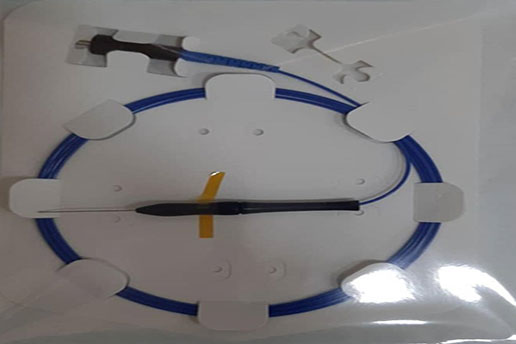

Disposable Polyimide Coated Single ring Radial Fiber

A single ring 400um to 600 um shaped fiber guarantee very high mechanical stability and excellent beam quality.

Properties |

Fiber type Loose Tube |

400 and 600um Colored Hytrel or without loose tube |

|

Fiber length |

2m |

|

Connector type |

SMA905 connector or HP-SMA905 |

|

Distal tip NA Sterilization |

Encapsulated angled tip 0.22 EtO-sterilized |

Application

Vascular, plastic, gynecological and ENT surgery

Hemorrhoids and fistulas, Endo-Lift.

Optional features

- extension sleeve available in various colors

- Laser inscription possible

- Customer-optimized designs on request

- Various accessories available

Clinical Tests has done by a group of specialized in diseases and laser surgery of the hemorrhoids and fistulas . (Iran, Nov. 2021). Results has been satisfactory on more than 40s patients.

Certifications & approvals: (In Progress)

Our production processes, devices and procedures is certified by ISO 13485 .

And Iran national medical device directorate (IMED)